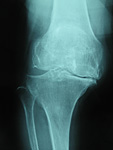

変形性膝関節症の分類

変形の進行に応じて、gradeⅠからgradeⅤに分類されます。

変形性膝関節症は、膝関節を構成する骨・軟骨や半月板、靭帯などの加齢による変性を基盤とし軟骨破壊や骨増殖によって変形を生じる疾患です。

変形性膝関節症は整形外科疾患の中で最も多く遭遇する疾患の一つで、その頻度は年々増加傾向にあり40歳以上の女性の61.5%、男性の42%にX線上で変形性膝関節症の所見がみられ、そのうち約90%以上の方が内側の変形を呈しています。